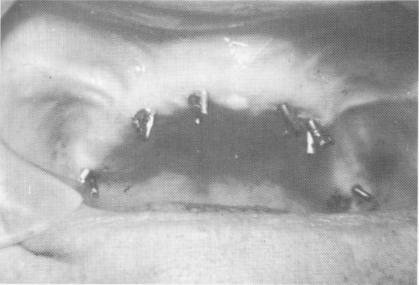

Fig. 10-219. All excess length of the pins was disked away.

The pins were then notched and cut short so that there would be no occlusal interferences (Fig. 10-219). Using the brush-on technique the pins were securely locked with one another with acrylic liquid and powder. After hardening, the acrylic cores were prepared for full crown restorations (Fig. 10-220). A full arch splint fabricated with all acrylic-overgold thimbles was then cemented over the prepared acrylic cores (Fig. 10-221). Radiographs reveal the finished case (Fig. 10-222). This case, and others done in this manner, lasted a few months longer than those done using the method presented in Case 22. However, none of the cases exceeded 14 months' duration. By that time the pins had loosened substantially enough to warrant removal of the entire